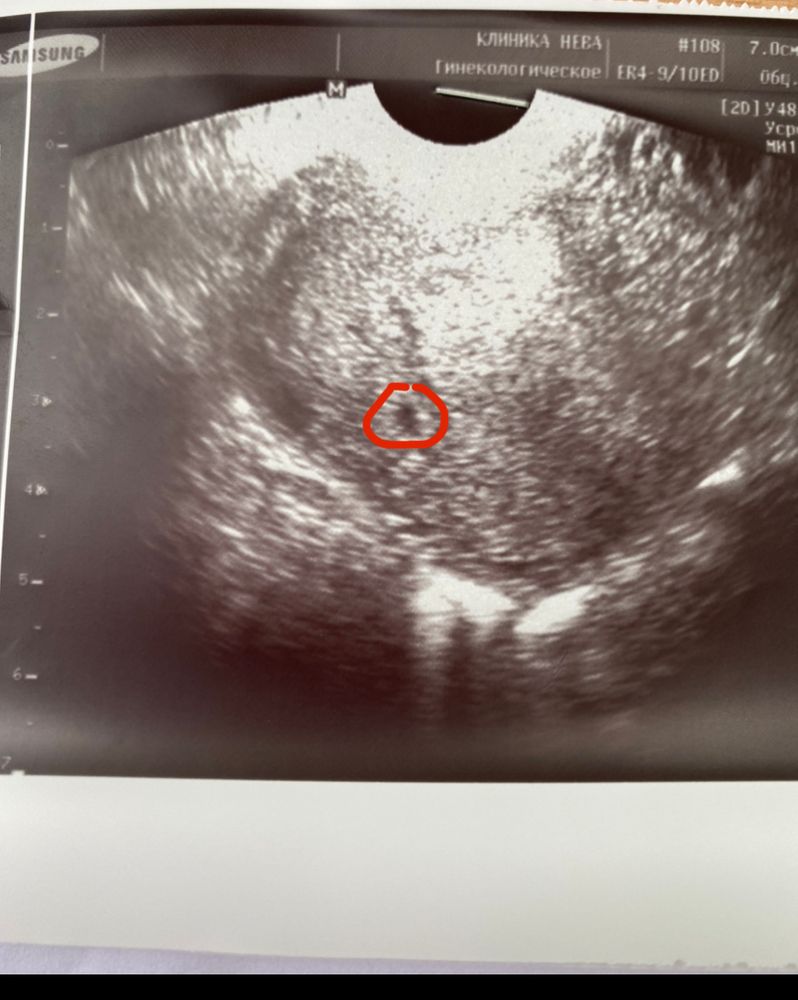

Вот и здорово! :) Обнаружили там, где и должен быть.

Анна, если новый, тогда отлично. Можно исключить внематочную так рано👍

Наташа, да . А у меня же аномалия труб , они длинные и загнутые . Поэтому высокий риск был 😬

Анна Ерёмина, нет ☺️ через определенное место 🙈 по животику ещё рано , не увидели бы

Анна Ерёмина, не слушайте никого ! Все будет хорошо ! У меня все прошло хорошо , не болит , не кровит ! В конце концов датчик не вилка 🥰 вам переживать нельзя ! Завтра увидите свою кроху , послушаете сердечко 😻🙏🏻